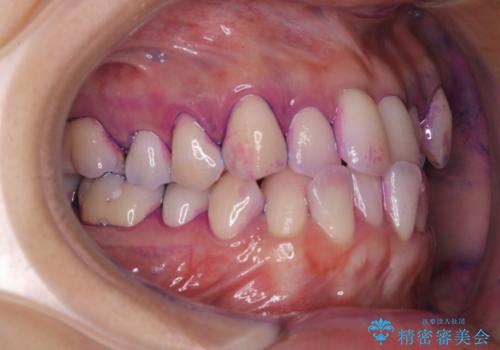

染め出し液を使ってプラークを染め出すことにより、普段の歯みがきで磨き残している場所を目で確かめることができます。

日々の歯磨きを上達するには、まずどこが磨けていないか認識することが大切です。